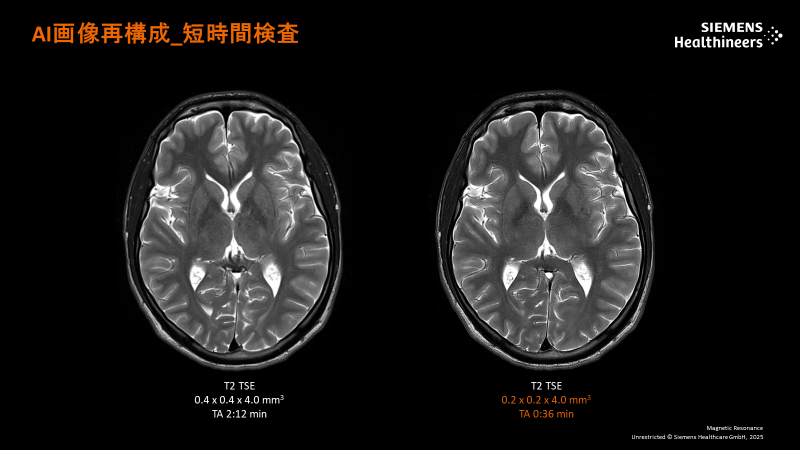

3Tの高い磁場強度とAIを用いて開発された最新のテクノロジーにより脳、脊椎などの微細病変、脳血管の小さい動脈瘤、全身各部位の高精細な画像検査を行うことができます。画像再構成プロセスにDeepLearning(深層学習) Reconstructionを用いたDeep Resolveは先進的なMR画像再構成技術です。撮像時間を短縮しても、従来と比較して高分解能な画像を得ることが可能になりました。また、呼吸停止ができない方でも、装置が自動的に呼吸情報を認識し、画像収集に反映されます。

Lumina MRA画像